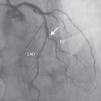

A 69-year-old man was referred for PCI of a 90% calcified lesion in the mid left anterior descending artery (LAD) involving the second diagonal branch (D2; Figure 1, arrow). After the left coronary ostium was cannulated and crossed with two BMW® wires, one to the LAD and other to the D2, predilation with a 2.5 mm×15 mm Trek® balloon was performed and an unsuccessful attempt was made to cross the stenosis with a 2.75 mm×22 mm Resolute Integrity® drug-eluting stent. Predilation was repeated with a 2.75 mm×15 mm Trek® non-compliant balloon at high pressure. Suddenly, balloon rupture was detected and the angiogram showed LAD rupture with extensive contrast extravasation into the pericardium (Figure 2, arrows; Video 1). Protamine sulfate was used to reverse the effect of heparin and the drug-eluting stent was deployed with balloon inflation for 10 minutes to seal the type III perforation but, as dye extravasation persisted, a 3.0 mm×19 mm GraftMaster® covered stent was superimposed, followed by rapid cessation of contrast leakage (Video 2). The D2 branch was lost (Figure 3, arrows), and periprocedural myocardial infarction occurred. The final image showed pericardial effusion (Figure 4; Video 3). The echocardiogram excluded tamponade. Forty-eight hours later, atrial fibrillation occurred with hemodynamic deterioration. Pericardiocentesis was performed and 50 ml of serosanguineous fluid was drained. Sinus rhythm was restored, with favorable evolution thereafter.